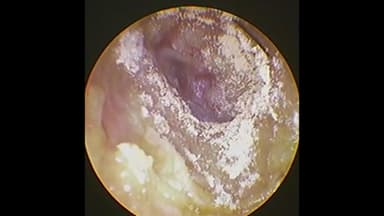

Nấm ống tai ngoài là tình trạng viêm ống tai ngoài do vi nấm. Bệnh nấm ống tai có thể gặp ở nhiều đối tượng khác nhau nhưng phổ biến hơn cả ở trẻ em do đặc điểm ở trẻ ống tai ngoài nhỏ, có nhiều lông và dịch nhầy, tạo điều kiện cho các loại nấm phát triển. Nhiều số liệu thống kê cho biết nấm ống tai chiếm khoảng 10% trong tổng số bệnh nhân bị viêm ống tai.

Người bệnh bị nấm ống tai ngoài thường có biểu hiện ngứa tai, tai như bị ướt, màng vảy trong ống tai… Lớp màng vày này do biểu bì ống tai ngoài bong tróc kết hợp với vi nấm tạo thành.